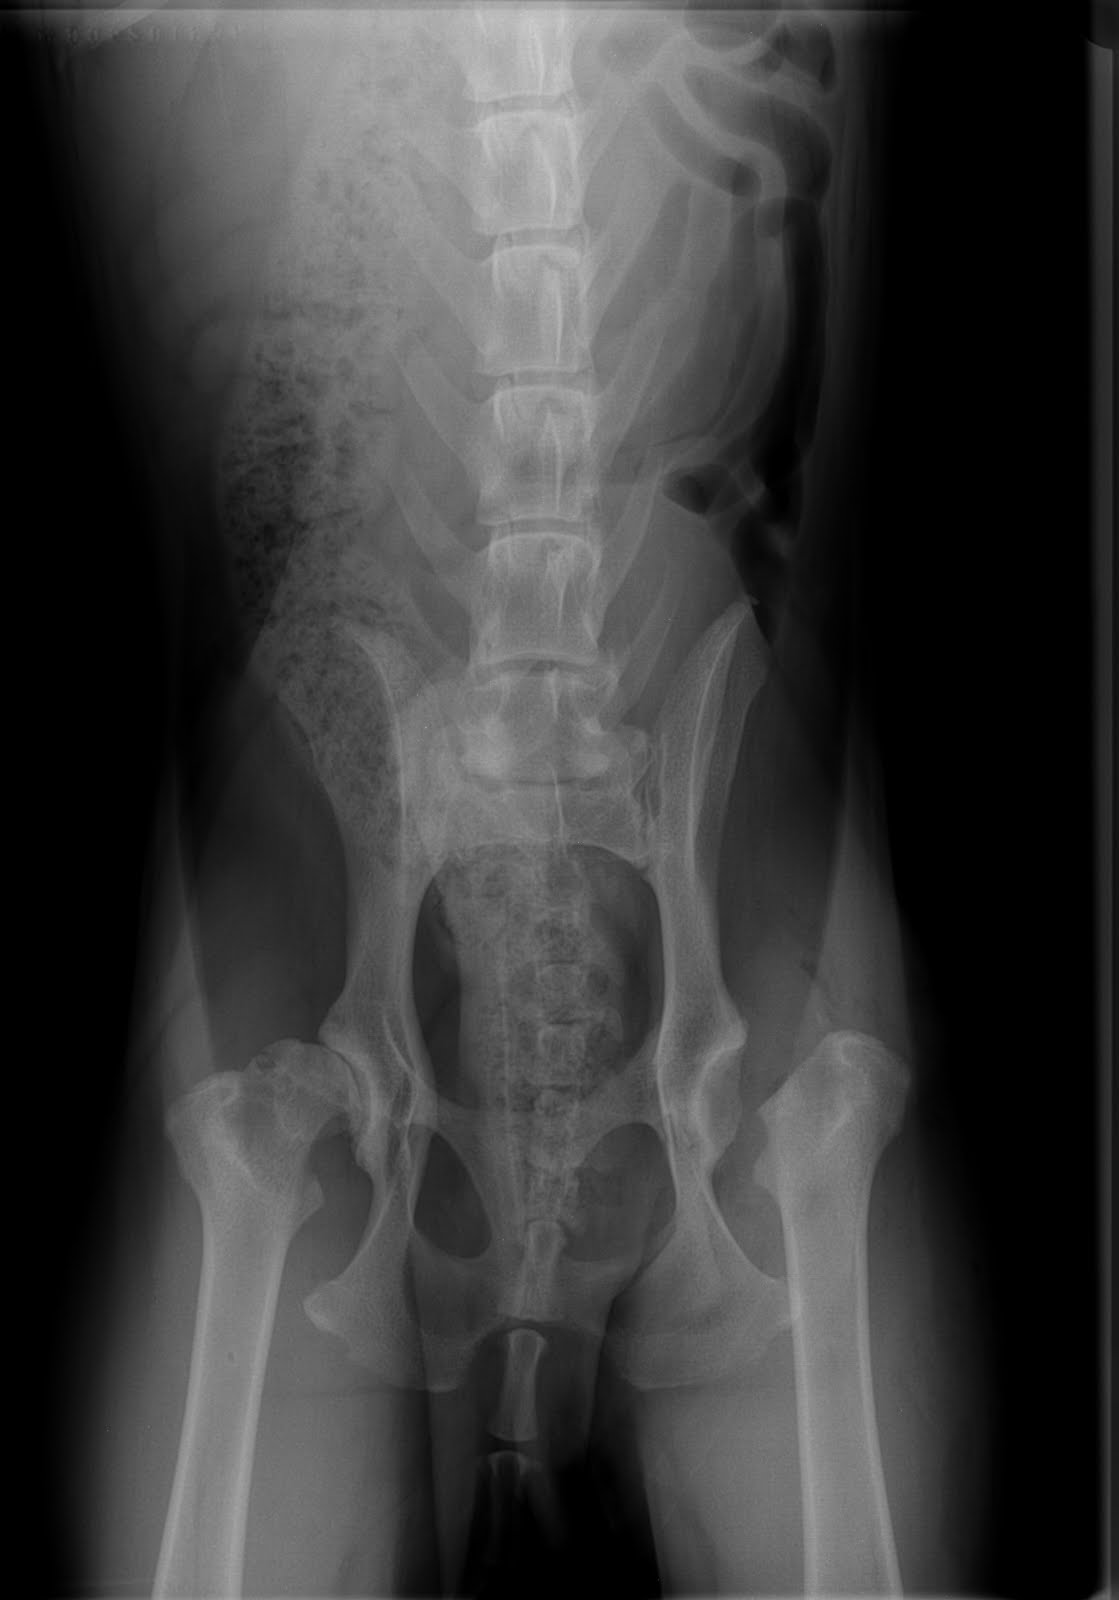

Xray Film Of Pelvis Dog Lateral View With Red Highlight On Hip Bone Hip Dysplasia Veterinary Partner Hip dysplasia occurs in many species (including humans and cats) but is mainly a concern in dogs. Hip dysplasia is typically a problem for large, stocky dog breeds. In a normal hip, the femoral head fits snugly inside acetabulum. It can occur in any breed or size of the dog. Hip dysplasia can occur in any breed or size of. Hip Dysplasia Veterinary Partner.